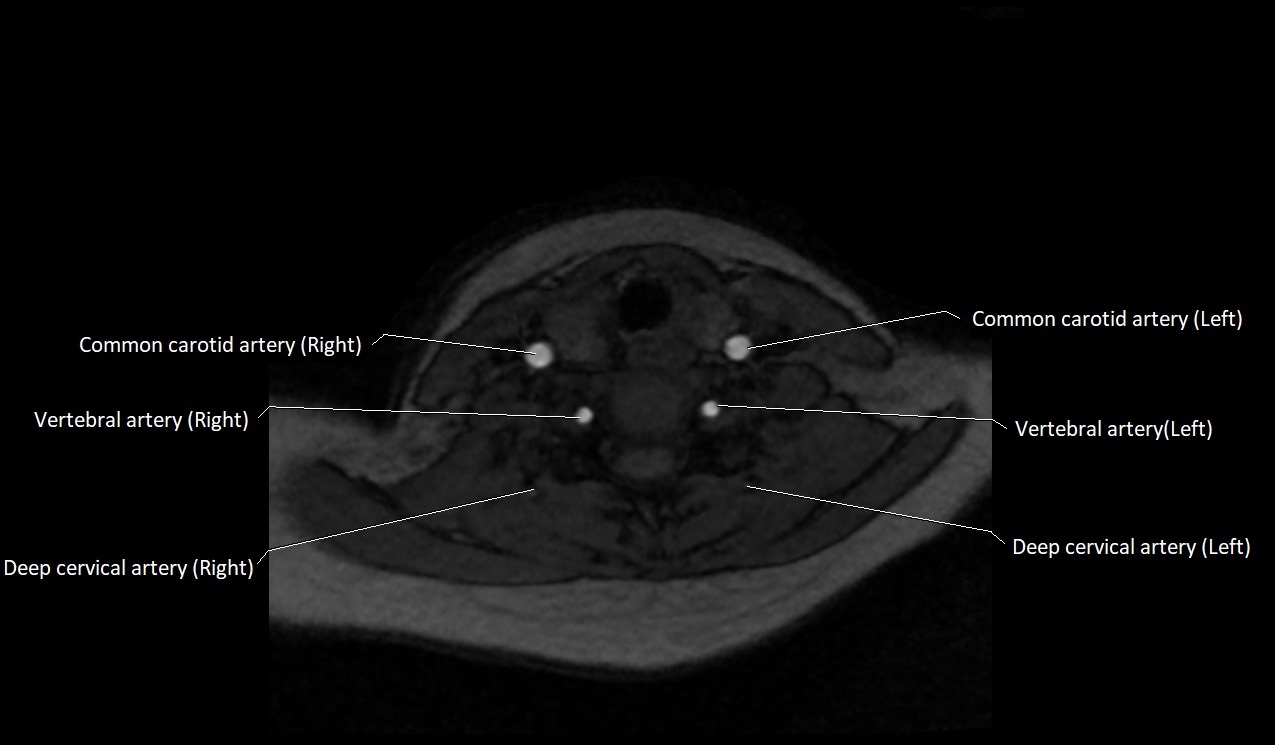

MRI Appearance:

• T1-Weighted Images:

• Appears as a tubular, hypointense (dark) structure relative to muscle

• May show flow void if the blood flow is fast

• T2-Weighted Images:

• Typically hypointense or isointense to muscle, but can be hyperintense if slow flow or stasis is present